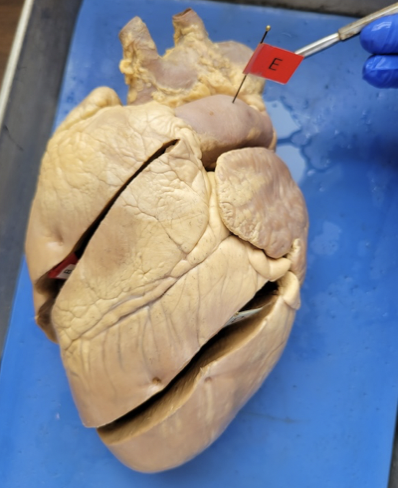

what is this

right ventricle